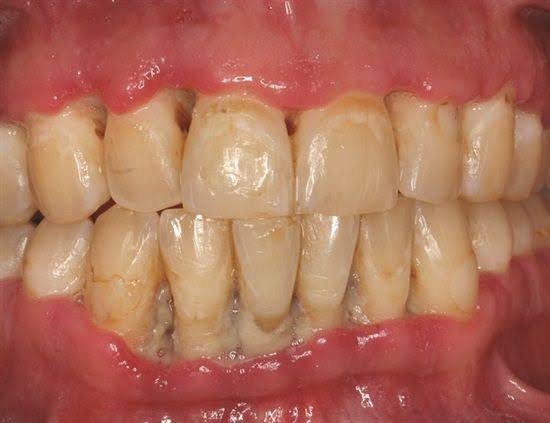

d. The interdental papillae are blunted, inflamed, edematous and hemorrhagic. Show Punched out crater like necrotic areas covered by grayish pseudo membrane

h. Gingiva is stained and teeth seem slightly to be extruded & moveable

– Interdental papillae show surface ulceration covered by a fibrinopurulent membrane.

– Underlying connective tissue shows acute/mixed inflammatory infiltrate along with extensive hyperemia.